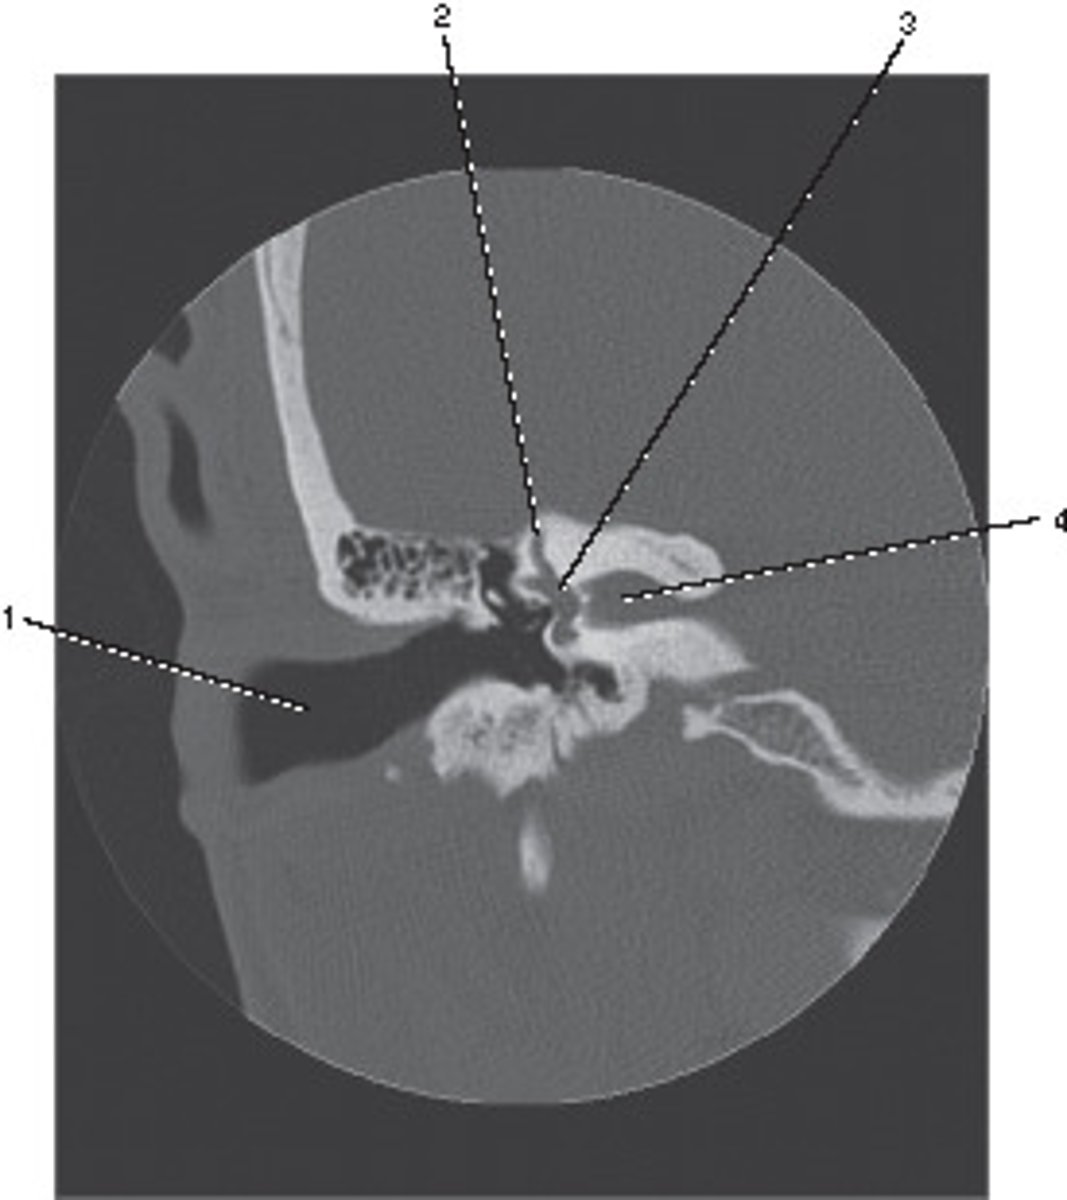

External Auditory Meatus

Number 3 corresponds to which of the following?

<p>Number 3 corresponds to which of the following?</p>

Semicircular Canal

Number 4 corresponds to which of the following?

<p>Number 4 corresponds to which of the following?</p>

Number 2 corresponds to which of the following?

<p>Number 2 corresponds to which of the following?</p>